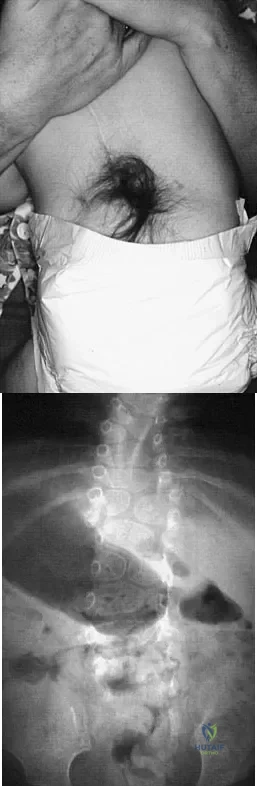

A 21-year-old football player had severe pain and immediate swelling in the left anteromedial chest wall while bench pressing near maximal weights several days ago. Examination at the time of injury revealed a mass on the anteromedial chest wall. Follow-up examination now reveals decreased swelling, and axillary webbing is observed. The patient has weakness to adduction and forward flexion. The injured muscle originates from the

The patient has a pectoralis major rupture, an injury that occurs most commonly during weight lifting. Grade III injuries represent complete tears of either the musculotendinous junction or an avulsion of the tendon from the humerus, the most common injury site. Examination will most likely reveal ecchymoses and swelling in the proximal arm and axilla, and strength testing will show weakness with internal rotation and in adduction and forward flexion. Axillary webbing, caused by a more defined inferior margin of the anterior deltoid as the result of rupture of the pectoralis, can be seen as the swelling diminishes. Surgical repair is the treatment of choice for complete ruptures. Nonsurgical treatment is associated with significant losses in adduction, flexion, internal rotation, strength, and peak torque. The pectoralis major originates from the proximal clavicle and the border of the sternum, including ribs two through six. The pectoralis major inserts (rather than originates) on the humerus. The coracoid process is the insertion site for the pectoralis minor, as well as the origin for the conjoined tendon. The pectoralis major has no attachment or origin from the scapula. The anterior deltoid originates from the lateral one third of the clavicle and the anterior acromion. Miller MD, Johnson DL, Fu FH, Thaete FL, Blanc RO: Rupture of the pectoralis major muscle in a collegiate football player: Use of magnetic resonance imaging in early diagnosis. Am J Sports Med 1993;21:475-477.